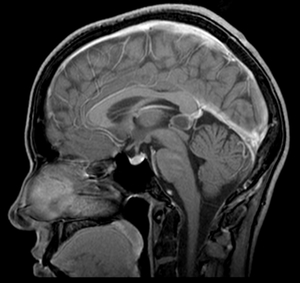

Наиболее распространенным методом визуализации для диагностики кист головного мозга является Магнитно-резонансная томография (МРТ). Этот метод позволяет получить детализированные изображения мозга и выявить наличие кист, их размер, локализацию и структуру. МРТ является неинвазивным и безопасным методом, который не использует ионизирующее излучение, что делает его предпочтительным для диагностики у детей и беременных женщин.

В некоторых случаях может быть назначена Компьютерная томография (КТ). Этот метод также позволяет визуализировать структуры мозга, однако он менее информативен по сравнению с МРТ, особенно для мягких тканей. КТ может быть полезна в экстренных ситуациях, когда необходимо быстро оценить состояние пациента, например, при подозрении на кровоизлияние или другие острые состояния.